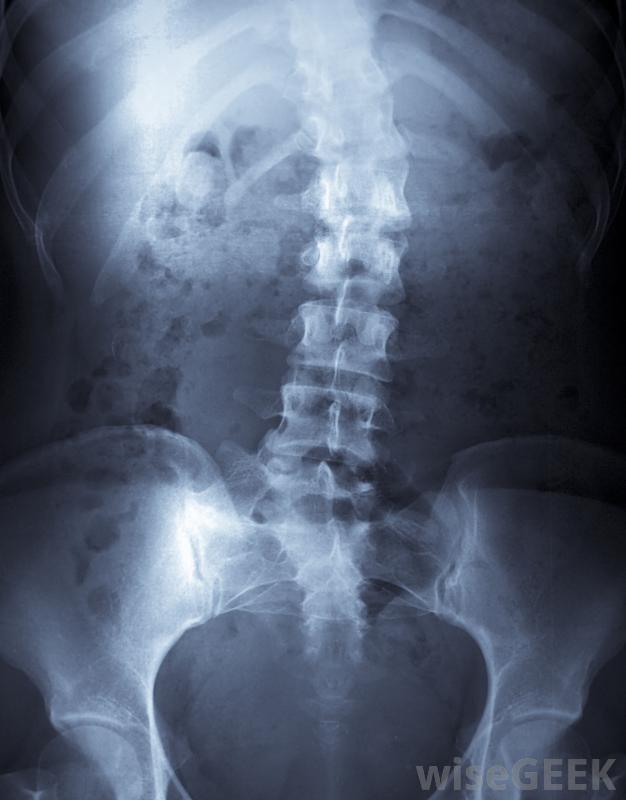

Cobb角是一種用于確定脊柱側凸患者或脊柱骨折導致彎曲程度的測量方法。這種測量方法有一些缺點,在將其用作診斷和治療工具時必須考慮這些缺點。Cobb角,也就是眾所周知的,相對容易評估,與患者的體格檢查相結合可作為一種有用的快速診斷工具。Cobb角用于測量脊柱側凸患者的脊柱彎曲程度為了確定Cobb角,需要對脊柱進行X光透視,從后面觀察患者。護理人員確定曲線的起點和終點,在曲線的起點和終點從椎骨上畫出直線。對于一個脊柱筆直的人來說,這些線是平行的。對于脊柱彎曲的人,這些線沿著椎骨的斜面,并且是成角度的背大括號有助于治療中度脊柱側凸。從這些線中劃出垂直線,直到它們相交為止。Cobb角是指醫生可能會根據彎曲度的嚴重程度,建議使用矯正器Cobb角的一個問題是測量時人們可能會偏離4到6度,這意味著支撐和手術的區別,這是一個相當嚴重的錯誤。脊柱側凸患者應咨詢幾位醫生,以獲得不同治療方案的意見此外,這項測量將脊椎視為X光片上的二維物體,當脊柱實際上存在于三維空間時,Cobb角不能解釋脊柱扭曲,這種扭曲通常伴隨著脊柱側彎的發展。患者可能有一個小的Cobb角,但是脊柱嚴重扭曲。一種解釋這一點的方法是不要僅僅根據Cobb角來推薦治療方法,而是在決定脊柱曲度的治療和處理時使用來自多個來源的信息脊柱脊柱側凸或外傷引起脊柱彎曲的患者通常需要脊柱專家進行治療。咨詢幾位醫生以獲得更多的意見是很有幫助的,因為治療理念可能是千變萬化的。當推薦治療方法時,詢問如何進行治療,為什么推薦,以及可用的替代方案是很重要的,這將幫助患者對治療做出明智的決定對脊柱進行x光檢查以確定Cobb角。